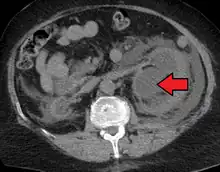

Massive hydronephrosis as marked by the arrow.- Renal ultrasonography of hydronephrosis[14]

- Stone causing hydronephrosis[14]